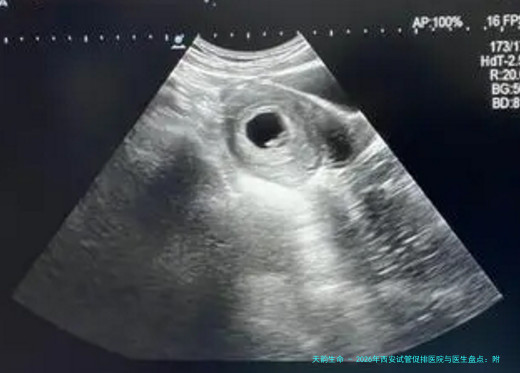

| 阴道B超卵泡监测(单次) | 150 | 80 | 120 | 100-150 |